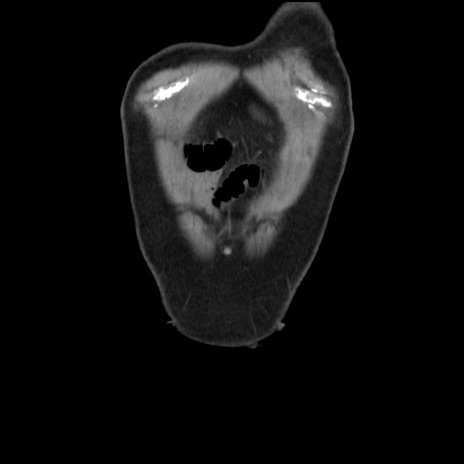

横断像

【症例】 70歳代男性

【主訴】 腹痛、嘔吐

【現病歴】 約1ヶ月前より間欠的に腹痛と嘔吐あり、当院消化器内科を受診したところCTで多発する肝臓のLDAを指摘され、精査中であった。以降は消化器症状は安定していたが、2日前より嘔気と腹痛があり、同日より排便・排ガスが消失した。改善認めず、 本日、救急外来を受診した。

【既往歴】 大腸ポリープ切除後。

【身体所見】意識清明・会話良好、BT 36.3℃、BP 127/80mmHg、 P 80bpm、腹部:膨満あり、平坦・軟、上腹部正中および下腹部正中に圧痛あり、反跳痛なし、筋性防御なし。

【データ】WBC 7200、CRP 0.77